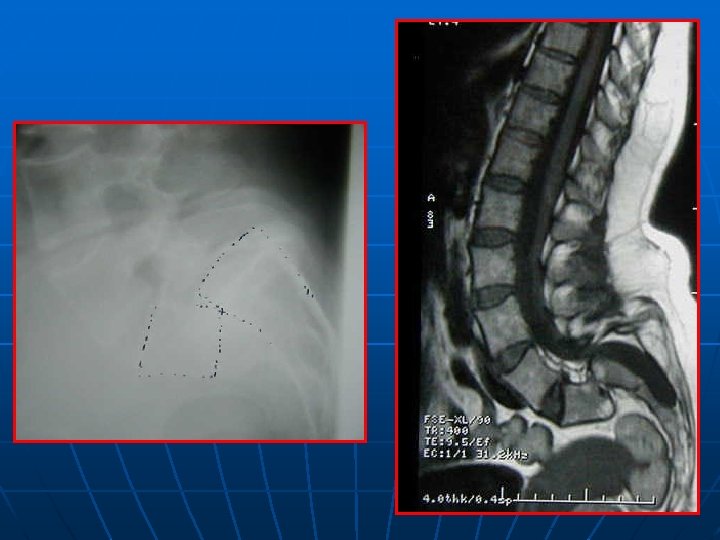

IRM n n EXAMEN CLE INCONVENIENTS : * statique * scoliose plan de coupe différent pour les étages STENOSE : centrale, foraminale ou associée (intérêt des coupes latérales foraminales) STRATEGIE OPERATOIRE+++ : ° état des disques (Modic? ) ° direction interligne articulaire : déstabilisation postopératoire?

SPONDYLOLESTHESIS ISTHMIQUE Rx standard: face+profil+3/4 D-G Découverte au stade de déplacement n Lombalgies isolées: pas d’autres explorations n Lombosciatiques: Rx dynamiques+ grand format+IRM ( TDM peu d’apport) n